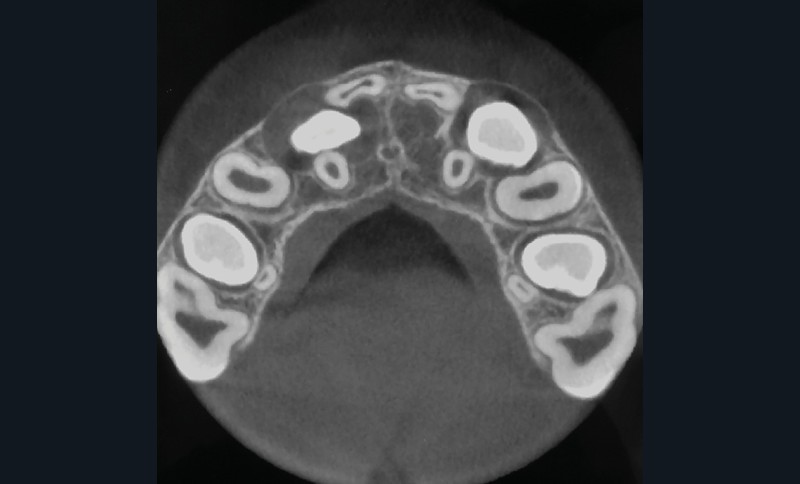

Le profil est convexe et associé à une inocclusion labiale au repos. Il s’agit d’une classe II squelettique sur un schéma facial normodivergent. Les rapports occlusaux sont de classe II bilatérale (complète au niveau molaire) avec des incisives inférieures vestibulo-versées. La 21 est géminée et la 11 vraisemblablement fusionnée avec un germe surnuméraire, sans altération de la formule dentaire. Du fait du diamètre mésiodistal fortement augmenté des incisives centrales, et du manque de place à l’arcade maxillaire qui en découle, les 12 et 22 sont en inversé d’occlusion en palato position. Les 53 et 63 sont persistantes sur l’arcade avec une inclusion en transposition incomplète de la 13, dont la cuspide se situe entre la racine de la 12 et celle de la 11 résorbée (fig. 1d-g).